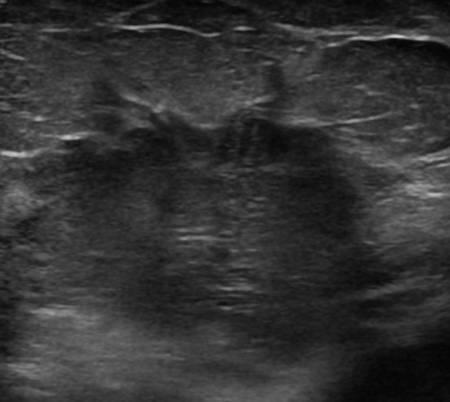

Ung thư vú

» Thông tin: Nữ giới – 76 tuổi.

» Lâm sàng: Khối tuyến vú.